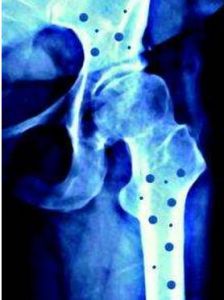

(1)關節病變:本病中關節炎發生最晚而且持續時間最長,通常是急性發作非對稱性、少數關節受累鶒,特別是下肢,以膝、踝、髖等負重關節最多見,其他的關節如腕指、趾脊柱也可累及。約20%的RS出現骶髖關節炎和上行性脊柱炎。易出現韌帶、腱鞘炎和足底筋膜炎症。大多數關節最終完全恢復少數持續性或復發性可發展為永久性臘腸樣指關節畸形。